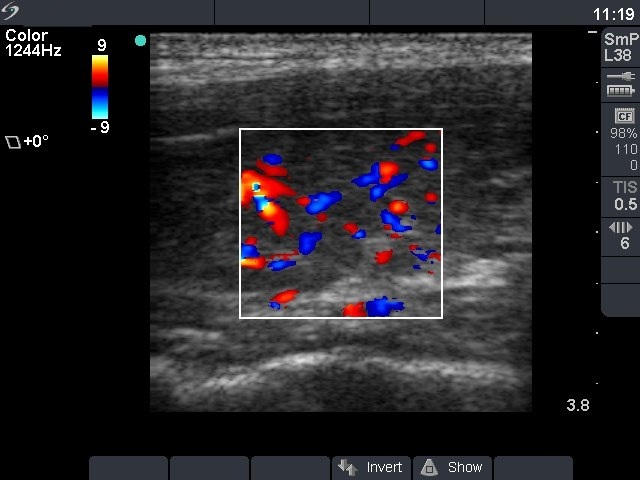

Second examination 4 months later (2nd row):

Clinical presentation: three months after discontinuation of methimazole therapy the patient had complaints suggesting recurrence of the hyperthyroidism.

Palpation: no abnormality.

Functional state: hyperthyroidism with TSH-level 0.02 mIU/L, FT4 33.1 pM/L.

Ultrasonography: the thyroids were hypoechogenic, and the vascularization was increased but not such an extent as observed at the first examination.

Clinical diagnosis: recurrent hyperthyroidism caused by Graves-Basedow's disease.

The patient was treated again with methimazole. 6 weeks later when FT4 level has normalized, the patient underwent radioiodine therapy.